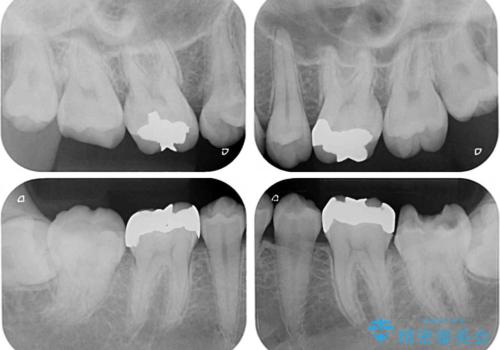

- 奥歯の虫歯と前歯のデコボコや突出感を気にして来院された患者様です。

上顎歯列が、下顎に対して前方にありましたが、口元に出っ歯の印象がなかったため、親知らずを抜歯した上で、上顎歯列全体を後方に移動させることとしました。

咬合力が強いため、アンカースクリューを使用し、ワイヤー装置にて矯正治療を行うこととしました。

矯正治療後は、奥歯の虫歯や銀歯を補綴・修復治療することとしました。